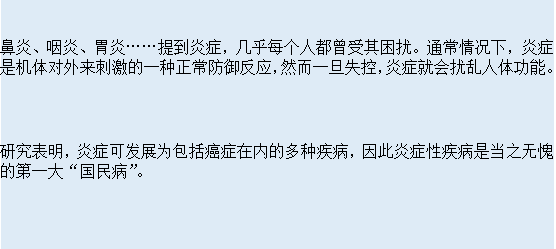

警惕!这5种慢性炎症若不及时治疗,竟可能演变为癌症!炎症,作为一种机体对抗损伤或感染的自我防护机制,常被视为良性生理过程。 然而,持续的炎症反应一旦转变为慢性,便可能演变为对健康的隐形威胁。 尤其值得注意的是,以下5种慢性炎症若得不到及时有效的治疗,甚至有可能演变成癌症。 1. 慢性胃炎:胃癌的潜在催化剂 由于幽门螺杆菌...

炎症隐患或演变为癌症?警惕身体三大预警信号,及时就医检查至关重要!从而为癌症的发生提供了“土壤”。 不幸的是,我们对炎症的警觉性不够高,很多人习惯了把一些常见的症状当作小问题,吃点药就当作解决了。 但实际上,炎症本身可能是一种信号,是身体在发出求救的声音,那么,怎样才能及时发现这些身体发出的信号呢? 适度的炎症反应是身体免疫系统...

短短一年炎症变癌症?提醒:碰上4类炎症不可拖,以免演变成癌每年1270万新癌症患者约六分之一是因感染病毒、细菌和寄生虫造成,这些感染导致了身体出现了长期的慢性炎症,时间长了,自然也就诱发癌症了。 所以,换句话说,慢性炎症是导致癌症的罪魁祸首,这并不夸张,作为医生,要提醒大家的是,碰上4类炎症不可拖,以免演变成癌。 第一,慢性萎缩...

不到一年时间,炎症变癌症了!医生坦言:患上3种炎症,尽早检查并最终演变为癌症。炎症的背后是什么?它和癌症如何联系在一起?炎症与癌症:看似无关的隐形杀手从医学角度来看,炎症是机体的一种基本保护反应机制。当身体遭受损伤或面临感染时,免疫系统会立即启动,旨在清除病原体并促进受损组织的修复。然而,我们必须认识到,这一机制并非绝...

短短一年炎症变癌症?医生提醒:患上4种炎症不能拖,小心癌变进而演变为癌症。就像是一颗慢慢发芽的毒瘤,早期无声无息地潜伏在体内,等到我们意识到时,病情已难以挽回。2018年,50岁的李女士因为长期... 如何预防这些炎症转变为癌症?炎症是人体的一种自我保护反应,但如果不及时控制,慢性炎症可能会成为癌症的温床。预防这些炎症引发癌症,首...

很多癌症都是自己拖出来的!提醒:这几种炎症别忽视,早治早好你有没有听过这样一句话:“健康就像存钱,平时积累一点点,关键时刻才有用。”可很多人不在乎,一直透支自己的身体,结果问题一拖再拖,等到检查出癌症,才发现后悔已经来不及了。 有些病,早发现早治疗,其实根本不至于演变成癌症,特别是一些小小的炎症,你有没有想过,那些看似不起眼...